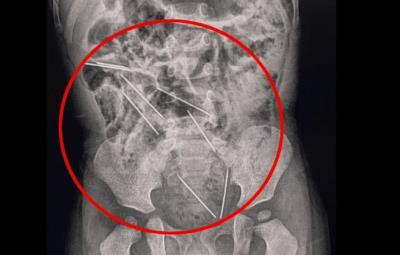

La madre del menor se percató de lo ocurrido, por lo que de inmediato fue llevado al hospital en donde fue sometido a una exploración, en donde radiografías mostraron que las agujas estaban dentro del sistema digestivo del niño.

Algunas de las agujas, se encontraban muy cerca de los órganos vitales del bebé, por lo que de inmediato los médicos lo sometieron a una cirugía de casi dos horas para retirar las agujas, y también recibió tratamiento por una pequeña lesión en el intestino delgado.De acuerdo con especialistas, cuando una persona traga un objeto extraño, este puede atorarse en el tracto gastrointestinal del esófago al colon, lo que le provocó una infección, una oclusión o ruptura en los órganos vitales.